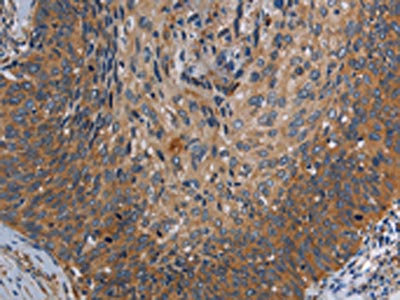

The image on the left is immunohistochemistry of paraffin-embedded Human ovarian cancer tissue using CSB-PA776699(PARP10 Antibody) at dilution 1/30, on the right is treated with synthetic peptide. (Original magnification: ×200)

The image on the left is immunohistochemistry of paraffin-embedded Human cervical cancer tissue using CSB-PA776699(PARP10 Antibody) at dilution 1/30, on the right is treated with synthetic peptide. (Original magnification: ×200)